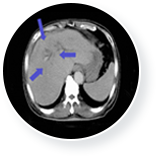

이때 3개월 간 매주 1회 일정으로 총 12회의 면역세포 치료를 실시하였고, 간암의 종양표 지자인 AFP가 치료 전 19,175(ng/ml)에서 치료 후 170(ng/ml)로 떨어졌습니다.

또한 CT검사 결과 간암의 축소 및 복수 소실이 확인되었습니다.

• 간암 치료 후  이미지

간암 치료 후